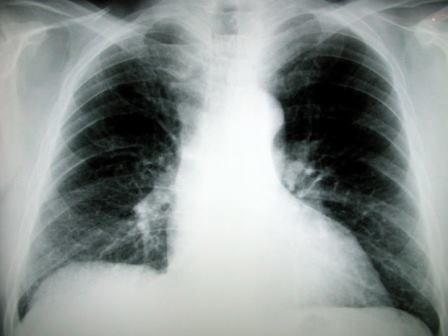

מחלת הריאות נגרמה עקב העבודה, הפיצוי: כחצי מיליון שקל

עובד במפעל שיש טען כי החשיפה לחומרים מסוכנים במסגרת העבודה היא שגרמה למחלה הקשה. בית המשפט קיבל את הטענה וקבע כי החברה התרשלה כשלא שמרה על בריאות העובד.

בשנת 2002 חש ברע, ולאחר שהתגלה כי הוא סובל ממחלת הריאות סיליקוזיס, הוא הפסיק לעבוד במפעל בהמלצת רופאה תעסוקתית. בשנת 2006, לאחר מאבקים משפטיים מול ביטוח לאומי, הוכר העובד כנכה בשיעור של 30% כתוצאה מחשיפה לאבק ואסבסט במסגרת העבודה.

בהתאם לחוות דעתו של מומחה בית המשפט, קבע השופט כי מחלת התובע נגרמה כתוצאה מחשיפתו לאבק השיש במהלך עבודתו במפעל וכי המעסיקה התרשלה.